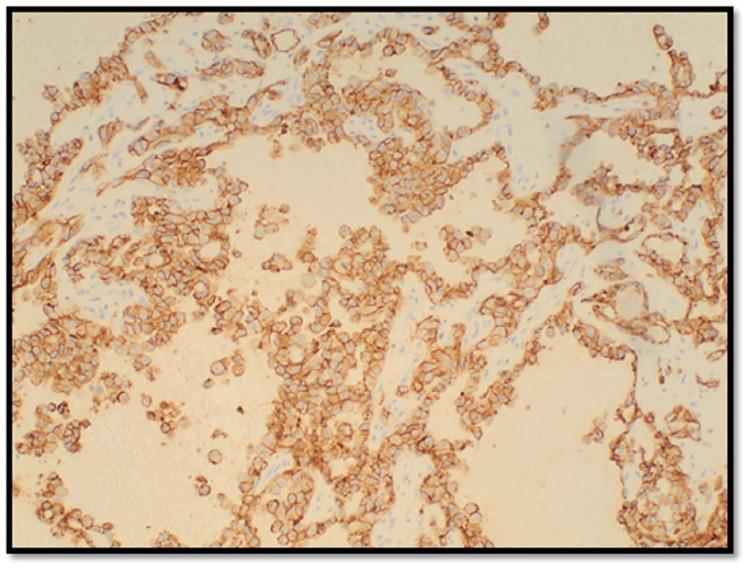

侵袭性曲霉菌与血管癌:一例肺侵袭性曲霉菌病合并上皮样血管肉瘤病例

The Ominous Aspergillus With Cancer of Blood Vessels: A Case of Invasive Aspergillosis and Epithelioid Angiosarcoma of the Lung.

Invasive aspergillosis occurs in the setting of risk factors such as severe or prolonged neutropenia, defects in cell-mediated immunity, and receipt of immunosuppressive therapy, particularly in patients with graft-versus-host disease (GVHD). Pulmonary epithelioid angiosarcomas (EASs) are rare malignant vascular tumors that are aggressive, frequently metastatic, and associated with a poor prognosis. We describe these two rare conditions occurring concurrently.

摘要

侵袭性曲霉病发生于存在严重或长期中性粒细胞减少、细胞介导免疫缺陷以及接受免疫抑制治疗等危险因素的情况下,尤其是在患有移植物抗宿主病(GVHD)的患者中。肺上皮样血管肉瘤(EAS)是罕见的恶性血管肿瘤,具有侵袭性,常发生转移,且预后不良。我们描述了这两种罕见情况同时发生的病例。